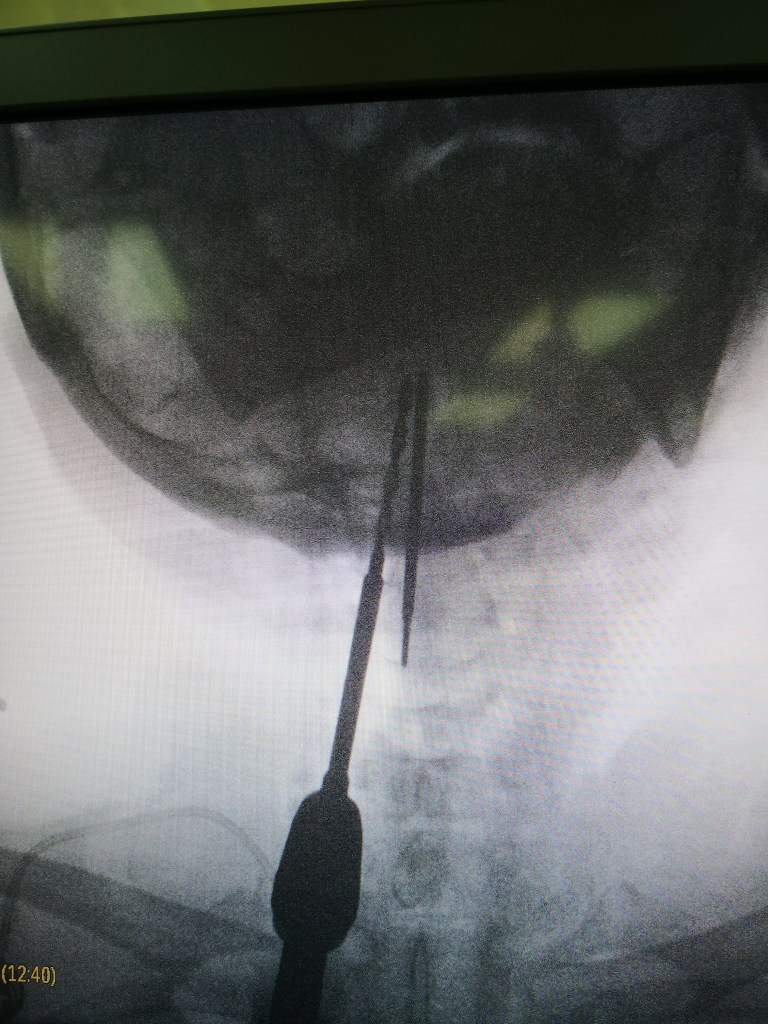

- Penetrating and retained foreign body involving orbit, paranasal sinuses and maxilla with CN2,3 palsy